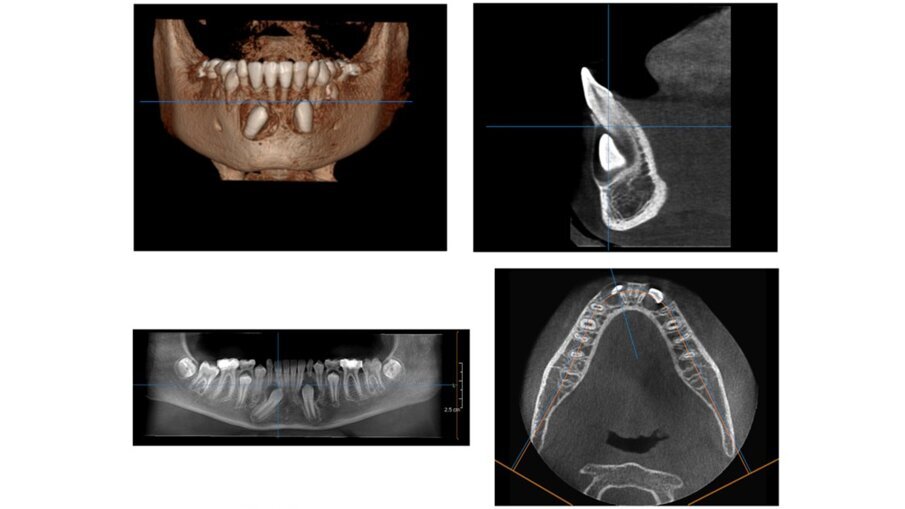

Il paziente, maschio, di 10 anni e mezzo, in dentizione mista. Le arcate dentarie sono in prima classe molare e canina. È presente un overjet di 1 mm e le linee mediane sono centrate. Si osserva un leggero affollamento in entrambe le arcate. Viene raccolta tutta la documentazione clinica per la valutazione del caso ed il successivo trattamento. Si procede alla presa delle impronte per i modelli da studio (Fig. 2). Vengono effettuate l’RX OPT (Fig. 3), la teleradiografia latero-laterale del cranio (Fig. 4) e l’analisi cefalometrica (Fig. 5, Tab. 1). Dopo un anno di terapia intercettiva, è stato eseguito un controllo con una rx OPT per valutare lo stato della permuta dentaria (Fig. 6). All’RX OPT si osserva l’inclusione intraossea con mesio versione dell’elemento 4.3. La CBCT è stata eseguita per valutare la posizione dell’CMI rispetto alle strutture anatomiche vicine (Fig. 7). Il CMI è stato valutato secondo la classificazione di Mupparapu5 nel tipo numero 1. Nella CBCT si osserva parte della corona del 4.3 a contatto con gli apici delle radici degli incisivi inferiori (4.1 e 4.2).

Fig. 7_CBCT: a) visione frontale, b) visione sagitale, c) overview, d) visione coronale.